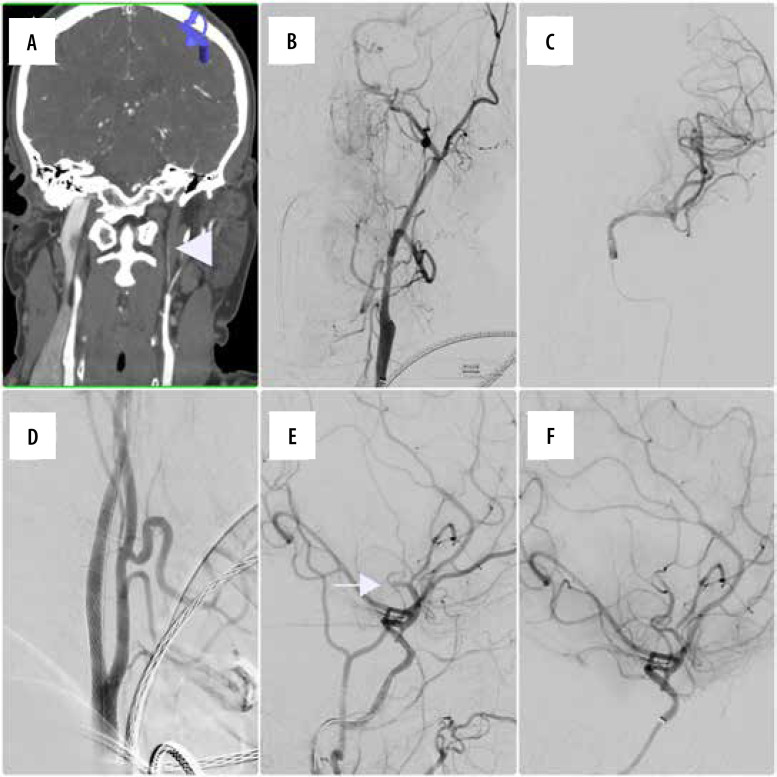

Purpose: Extracranial internal carotid artery dissections (EICAD) remain a relatively common cause of ischaemic events in young patients. Currently, there is no consensus on standardised use of endovascular therapy in the treatment of these patients, but available data suggest that conservative treatment is not sufficient in 15% of cases. The aim of our study was to evaluate if endovascular stent placement was safe and effective for the treatment of extracranial internal carotid artery dissection, and whether it should be considered in properly selected patients.

Material and methods: This single-centre, retrospective study aimed to evaluate procedural and clinical outcomes of patients with EICAD who underwent endovascular stenting between 2015 and 2024. Procedural and clinical efficacy and safety, the rate of complications, and long-term outcomes were noted.

Results: A total of 21 patients (10 females) with an average age of 53 years underwent stenting for EICAD. Technical success was achieved in all cases. Perioperative complications were noted in 2 cases. Neurological evaluation performed at 6-month follow-up showed very good clinical results in the majority of cases (mRS 0 and mRS 1 were 76% and 19%, respectively). Control imaging examinations confirmed stent patency in all cases. No long-term mortality was observed.

Conclusions: This retrospective study demonstrated procedural and clinical safety and efficacy of endovascular stenting in patients with extracranial internal carotid artery dissection. That is why endovascular therapy should be proposed to individuals with unsatisfactory response to medical treatment and in cases of disease progression.